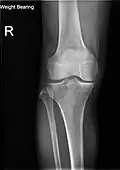

X-ray

-

Knee X-ray -

Knee X-ray (weight bearing) -

Knee X-ray (weight bearing, flexion)